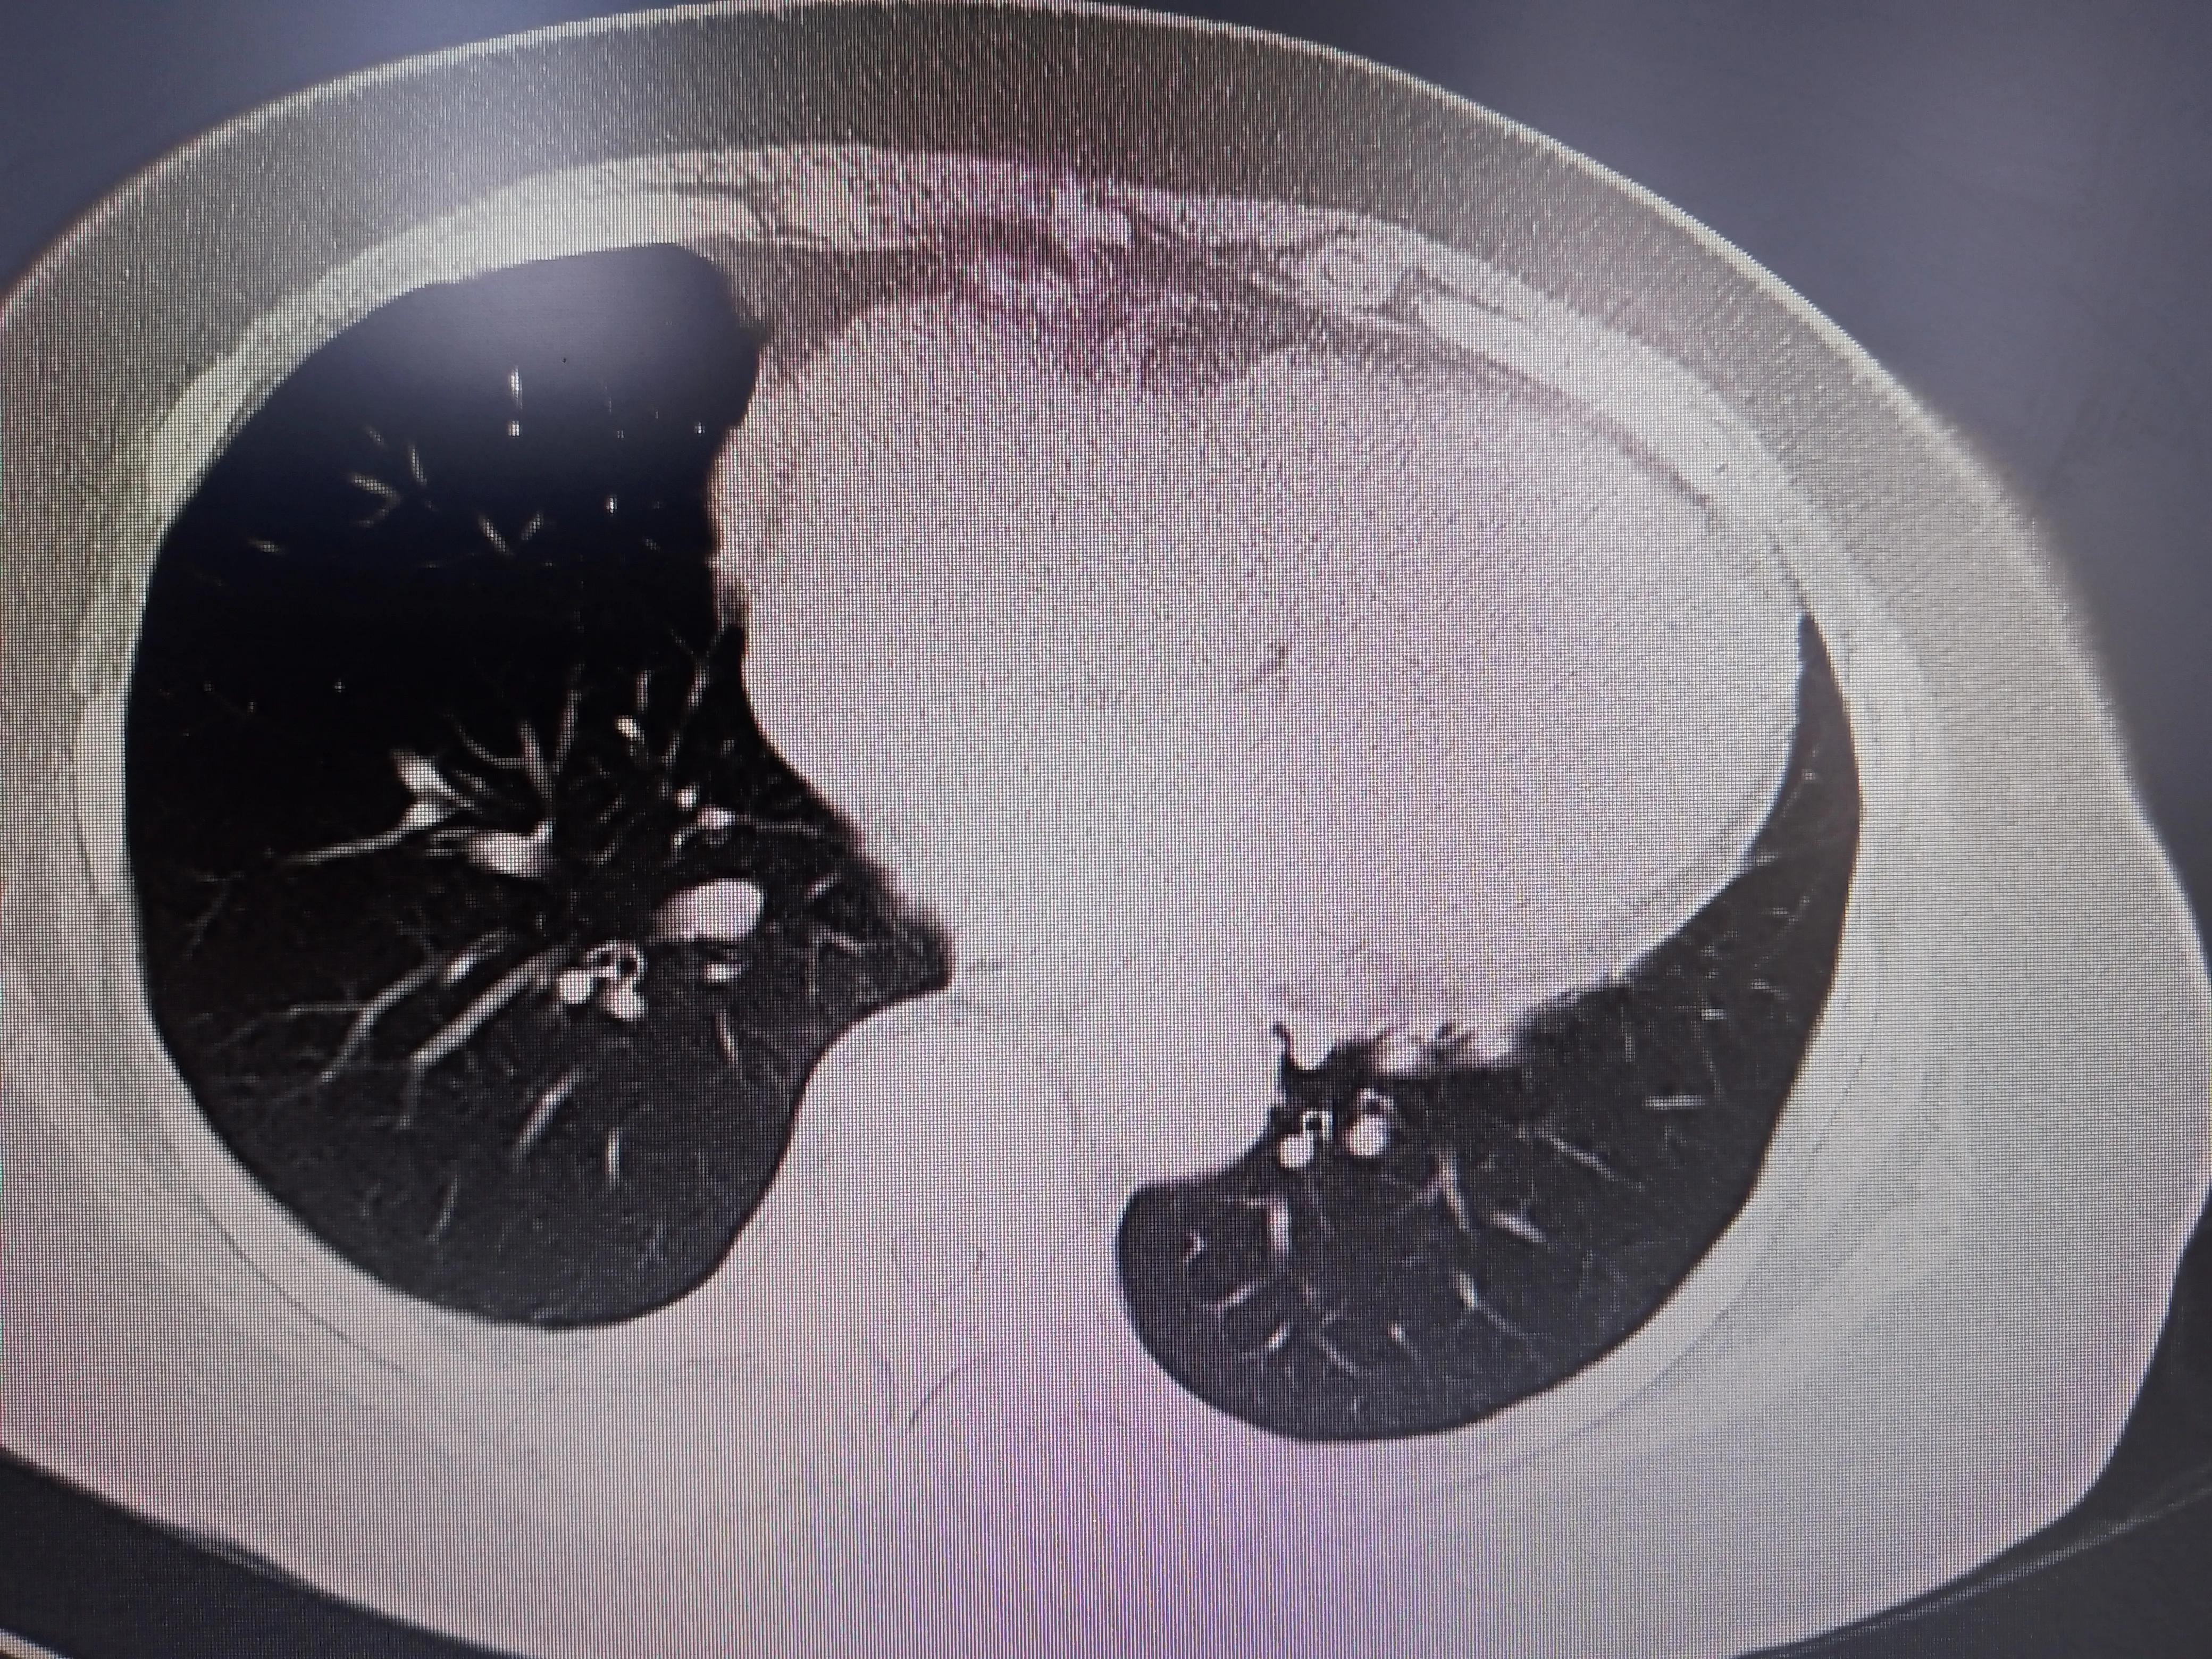

体检可基本排除膈肌麻痹,做了肺静脉CT,排除了肺静脉狭窄或闭塞

左心耳封堵尚可,边缘微量残余漏;

同时肺静脉CT里面发现肺里很干净,没有结节也没有明显的急性或慢性炎症;右心明显扩大导致心尖上翘。

右心明显扩大,肺挺干净的